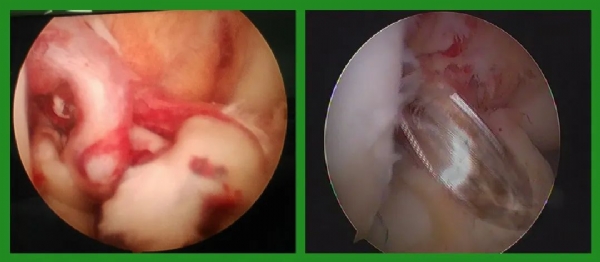

(术中)

(关节镜下损伤的和重建完成的韧带)